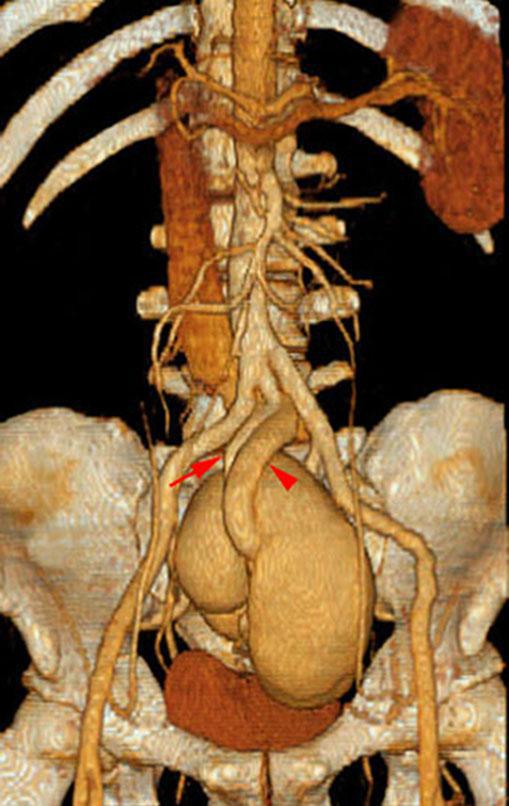

Riñón único pélvico